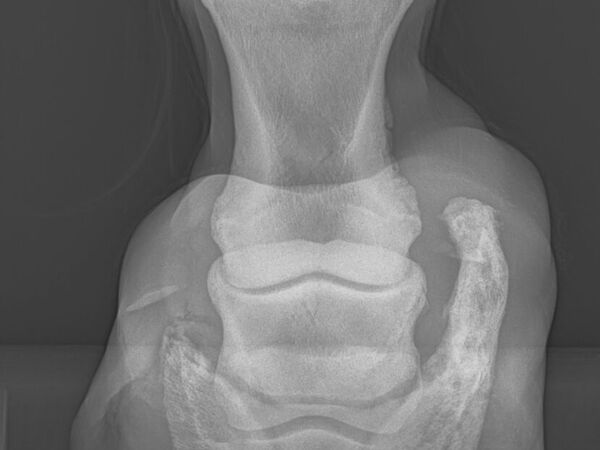

• Radiographie

Appareil numérique permettant de faire des clichés radiographiques à la clinique ou à domicile.